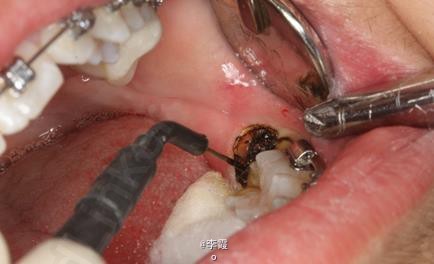

患者、马xx、15岁,主诉:牙齿不齐,要求正畸治疗。 转诊外科行下颌升支处种植体支抗直立下颌磨牙。通过患者的术前影像资料,47牙冠远中有部分骨质覆盖牙冠,采取翻瓣导萌直立磨牙。37采取电刀环切导萌直立磨牙。